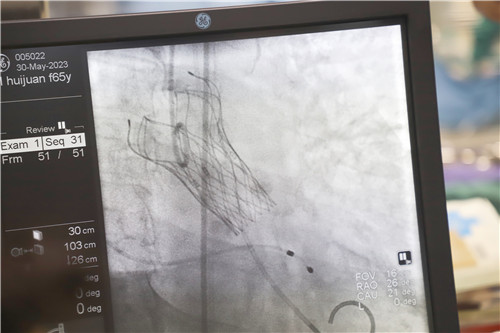

為保證創(chuàng)傷小、恢復(fù)快、并發(fā)癥可控,心血管內(nèi)科聯(lián)合麻醉科、醫(yī)學(xué)影像科、超聲醫(yī)學(xué)科等多學(xué)科會(huì)診,反復(fù)溝通討論,最終決定施行TAVR手術(shù),并征得王女士及家人的同意。該項(xiàng)微創(chuàng)介入技術(shù)對(duì)術(shù)者的技能操作水平和醫(yī)院的綜合救治能力要求極高,從大腿股動(dòng)脈置入導(dǎo)管,再通過(guò)導(dǎo)管將人工生物心臟瓣膜輸送至已經(jīng)病變狹窄的瓣膜位置,取代其瓣膜功能。

不為良相,便為良醫(yī)。石化醫(yī)院心血管內(nèi)科團(tuán)隊(duì)在汪念東副院長(zhǎng)的帶領(lǐng)下和皖南醫(yī)學(xué)院弋磯山醫(yī)院湯圣興教授的指導(dǎo)下,術(shù)中利用豬尾管懸吊AL1導(dǎo)管增強(qiáng)同軸跟進(jìn),經(jīng)過(guò)多學(xué)科四個(gè)小時(shí)的緊張救治,最終建立軌道成功置換瓣膜。

王女士術(shù)前測(cè)壓力階差高達(dá)110mmHg,在置換瓣膜后,壓力階差恢復(fù)到5mmHg,且無(wú)瓣周漏,在麻醉蘇醒后恢復(fù)了自主心率和自主呼吸。